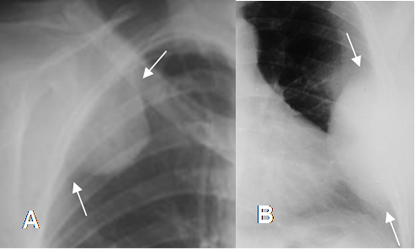

Fig 38. Lesiones extrapleurales.

A y B: Rx PA. Imágenes densas y de bordes bien definidos, que forman ángulos obtusos con la pared costal, indicando ubicación extrapleural.